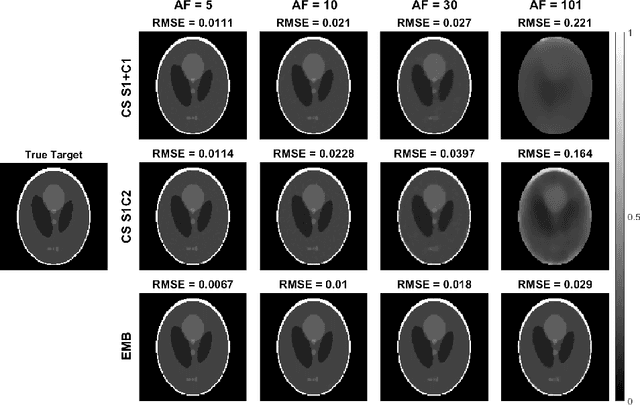

Abstract:Quantitative MRI (qMRI) methods allow reducing the subjectivity of clinical MRI by providing numerical values on which diagnostic assessment or predictions of tissue properties can be based. However, qMRI measurements typically take more time than anatomical imaging due to requiring multiple measurements with varying contrasts for, e.g., relaxation time mapping. To reduce the scanning time, undersampled data may be combined with compressed sensing reconstruction techniques. Typical CS reconstructions first reconstruct a complex-valued set of images corresponding to the varying contrasts, followed by a non-linear signal model fit to obtain the parameter maps. We propose a direct, embedded reconstruction method for T1rho mapping. The proposed method capitalizes on a known signal model to directly reconstruct the desired parameter map using a non-linear optimization model. The proposed reconstruction method also allows directly regularizing the parameter map of interest, and greatly reduces the number of unknowns in the reconstruction. We test the proposed model using a simulated radially sampled data from a 2D phantom and 2D cartesian ex vivo measurements of a mouse kidney specimen. We compare the embedded reconstruction model to two CS reconstruction models, and in the cartesian test case also iFFT. The proposed, embedded model outperformed the reference methods on both test cases, especially with higher acceleration factors.